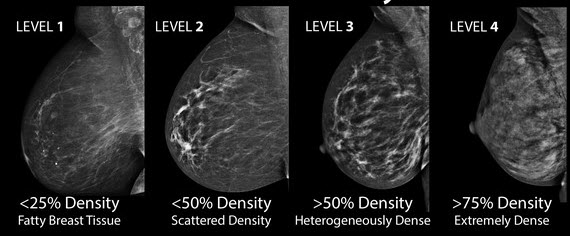

The woman who has inflammatory breast cancer has breast cancer that's red and inflamed, with an angry look to the breast cancer, he says. What does breast cancer look like? Googled and freaking out about ibc. The problem is that inflammatory breast cancer can look very much like mastitis early on, and is often diagnosed only after a woman has been treated first for mastitis (often with no improvement in symptoms). Mammogram imaging may show skin thickening, but often there is no distinct mass found on physical examination or …

These tubes, which are hollow, allow lymph fluid to drain out of the breast. The problem is that inflammatory breast cancer can look very much like mastitis early on, and is often diagnosed only after a woman has been treated first for mastitis (often with no improvement in symptoms). Kathleen ruddy inflammatory breast cancer accounts for approximately 5% of all cases of invasive breast cancer in the united states. Inflammatory breast cancer is often misdiagnosed because it is so rare, and is difficult to treat because it is particularly aggressive. A small red spot that looks very much like an insect bite or rash can be an early sign of ibc. Because ibc grows quickly, it is usually found at a locally advanced stage, meaning that cancer cells have spread into nearby breast tissue or lymph nodes. Googled and freaking out about ibc. The woman who has inflammatory breast cancer has breast cancer that's red and inflamed, with an angry look to the breast cancer, he says. Online says it develops suddenly. However, these signs and symptoms are most often associated with benign breast conditions. Inflammatory breast cancer (ibc) is rare, making up about 2 to 4 percent of breast cancer cases. Other ultrasound findings that suggest breast cancer include: The breast tissue deflects these waves causing echoes, which a computer uses to paint a picture of what's going on inside the breast tissue (no radiation is involved).

Most inflammatory breast cancers are invasive ductal carcinomas, which means. Inflammatory breast cancer accounts for between 1% and 5% of breast cancers and women do not usually have a lump and it doesn't usually. There is a pink area about the size of a quarter on the outside of my breast now for about a week with no change. Finding breast lumps and seeing change in the size and shape. Other ultrasound findings that suggest breast cancer include: This is referred to as peau d'orange, which is french for orange skin and it is caused by cancer cells blocking the lymph vessels beneath the skin, which have formed into ridges or tiny lumps. That indicates that the lesion likely contains a variety of elements, which may or may not indicate breast cancer. It often does not cause a breast lump, and it might not show up on a mammogram. In view of those symptoms often occur, and errors in diagnosis of patients treated for inflammatory diseases, that happen to be named and are known as these forms breast cancer. Ibc doesn't look like a typical breast cancer. This is a particularly aggressive cancer and i had chemo;bilateral mastectomy and radiotherapy ending at end of oct 09. I have inflammatory breast cancer which was firstly diagnosed as mastitis in jan 09. Learn more about ibc including the warning signs, diagnosis.